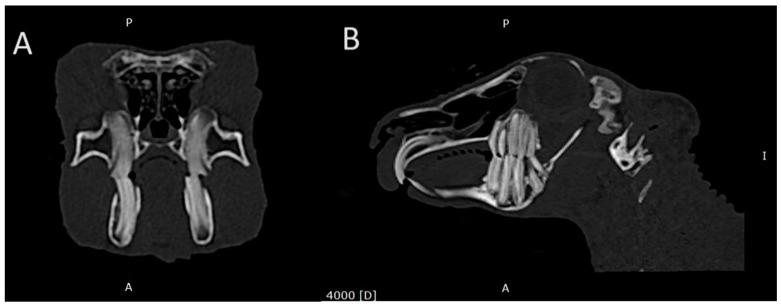

Domestic rabbits have teeth that grow throughout the animal's life and are prone to disease. Clinical signs of dental disease in domestic rabbits are non-specific, and, therefore, a definitive diagnosis usually requires additional methods. This study was carried out on a group of 105 domestic rabbits aged 3 to 9 years. In total, 90 domestic rabbits with dental disease visible on CT images and other secondary diseases of the head area qualified for this study. Malocclusion was found in 57 (63.3%). Retrograde elongation of the tooth apices in the mandible was present in 39 (43.3%), and it was present in the maxilla in 48 (53%). Clinical tooth crowns were overgrown in 39 (43%). Dental abscesses were present in 54 (63%). Secondary to the presence of a dental abscess, osteomyelitis was found in 43 (79% of the animals with a dental abscess). Dental inflammatory resorption was found in 36 (40%). Secondary to dental disease, nasal cavity inflammation was found in 18 (20%). Otitis media was present in six (6.7%). The most common dental disease found in this study's animals was malocclusion secondary to abnormal clinical crown abrasion and abnormal tooth growth. In domestic rabbits, osteomyelitis is a common complication of dental abscesses. Computed tomography is an invaluable diagnostic method in the diagnosis of dental disease and secondary diseases of the head area, such as inflammation of the nasal cavities or otitis media, in pet rabbits.

家兔的牙齿会在其一生中不断生长,且容易患病。家兔牙齿疾病的临床症状不具有特异性,因此,通常需要借助其他方法才能做出明确诊断。本研究针对105只年龄在3至9岁的家兔展开。共有90只家兔符合研究条件,这些家兔在CT图像上可见牙齿疾病以及头部区域的其他继发性疾病。其中,57只(63.3%)存在错牙合。下颌骨牙尖逆行伸长的有39只(43.3%),上颌骨有48只(53%)。临床牙冠过长的有39只(43%)。存在牙脓肿的有54只(63%)。继发于牙脓肿,发现43只患有骨髓炎(占患有牙脓肿动物的79%)。发现牙炎性吸收的有36只(40%)。继发于牙齿疾病,发现18只患有鼻腔炎症(20%)。患有中耳炎的有6只(6.7%)。本研究中家兔最常见的牙齿疾病是继发于临床牙冠异常磨损和牙齿异常生长的错牙合。在家兔中,骨髓炎是牙脓肿的常见并发症。计算机断层扫描在诊断宠物兔的牙齿疾病以及头部区域的继发性疾病(如鼻腔炎症或中耳炎)方面是一种非常有价值的诊断方法。